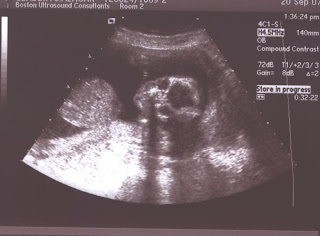

The pics

Here they are...

I was going to choose the best, but decided to just go ahead and post them all. The alien-like ones are frontal views, looking down at the baby. The profiles are pretty self-explanatory. Note that you can see a little foot kicking in the left corner of one of the profiles, and you can see the hand in two of the others. Pretty neat, huh?